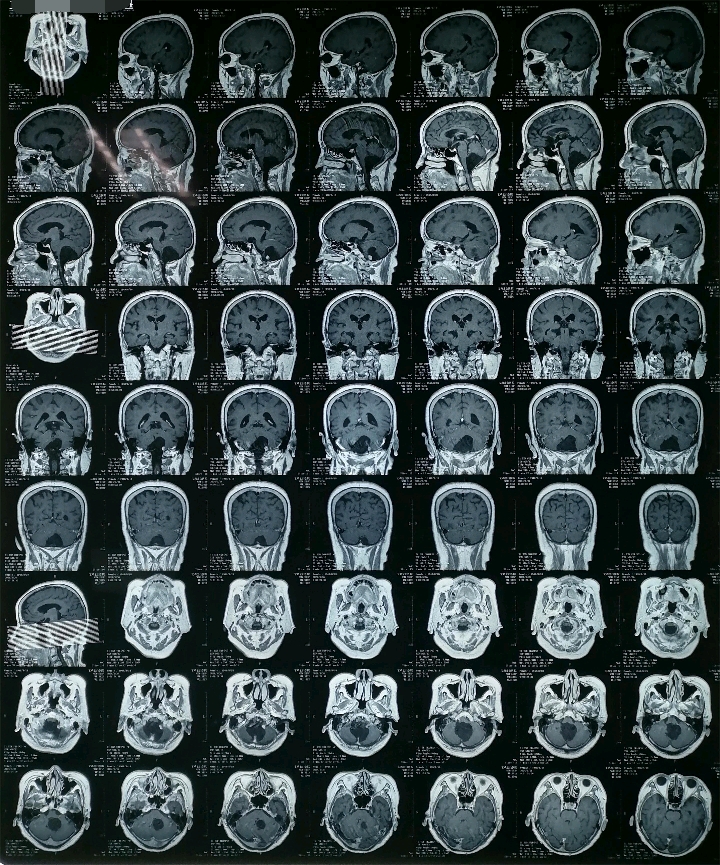

初步诊断:枕大孔区占位性病变 血管母细胞瘤

术前资料

手术方案

俯卧位,后正中入路,枕大孔区肿瘤切除术+脑室外引流术